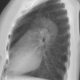

Болеет с 2007 года, при бронхоскопии поставлен диагноз гемосидероза легких, но картина не вполне в него укладывается. Прогрессирующая одышка. Проф.вредностей и сопутствующих заболеваний нет. КТ выполнялась впервые. Рентгенограммы не представлены, поэтому показываю КТ-реконструкцию=симуляцию рентгенограмм. Случай-демонстрация.

Реконструкции

КТ-реконструкция ID:58116

КТ ОГК ID:58120

Лимфангиолейомиоматоз легких.

Точно интерстициальное заболевание. Необходимо дифференцировать между гистоцитозом X и ЛАМ. Отграниченный пневмторакс с обеих сторон.

Для гистиоцитоза более характерна неправильная форма кист с преобладанием в верхних отделах легких, чего в данном случае не наблюдается - кисты тонкостеннные и распределены равномерно по всем легким. Плюс пациентка не курила и не курит (ассоциация с курением в 95% случаев гистиоцитоза легких).

Для гистиоцитоза также характерны узелки. В представленном случае есть множественные узелки до 13 мм диаметром, с распределением больше в периферических зонах, некальцинированные, мягкотканные плотностью до 30 едН. При гистиоцитозе с таким распространенным поражением будет присутствовать фиброз, как при любом "запущенном" гранулематозе, а в данном случае архитектоника легких не нарушена.

Пневмоторакса нет, это субплевральные более крупные кисты, срасположены вдоль междолевых щелей с обеих сторон, вытянутой неправильно веретенообразной формой напоминают осумкованную жидкость. Сосуды проходят по стенке этих кист, а при пневмотораксе между воздухом в плевральной полости и сосудом всегда будет участок спавшейся легочной паренхимы.

Случай интересен именно узелками.

Такие узелки можно спутать с метастатическим поражением.

При ЛАМ определяется два типа узелков, матового стекла и солидные.

Матового стекла узелки - мультифокальная микронодулярная гиперплазия пневмоцитов, характерная для ЛАМ, ассоциированного с туберозным склерозом (но в ряде работ указывается на возможность появления узелков до 2 см вне связи с ТС). http://pubs.rsna.org/doi/full/10.1148/radiol.2421051767

Солидные узелки - доброкачественные пролиферативные узелки, гистологически характерные для ЛАМ (хотя встречаются не часто), состоящие преимущественно из веретенообразных клеток.